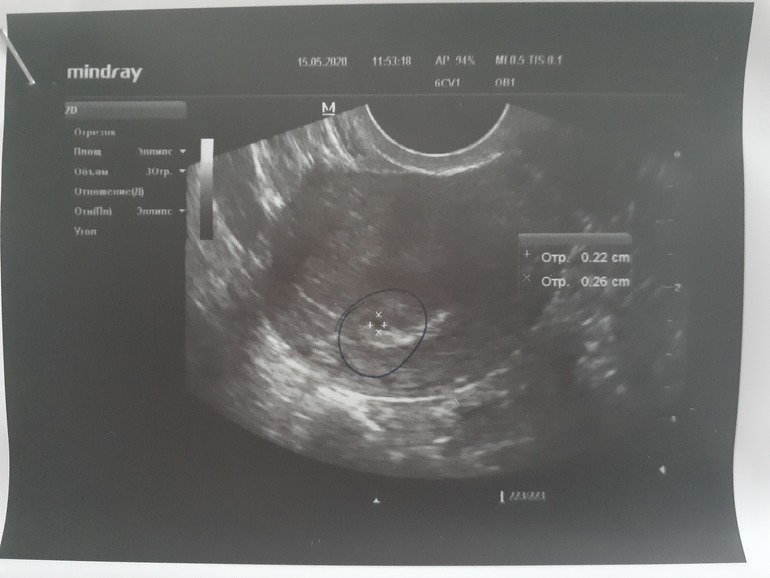

Девочки привет!!! Моя долгожданная беременность наступила и я очень счастлива 🥰 последние месячные 14 апреля, очень тянет низ живота справа, решила сходить на узи исключить вб, понимаю что рано, но очень переживала. По результатам узи в матке плодное яйцо 2.5 мм. Но жт четко не определяется! Сказали прийти через 3 недели повторно. У кого так было что жт не определялось или не было вообще? И благополучно ли завершилась беременность?

А включение в яичнике, либо сама киста ЖТ, либо ЖТ не видно из-за кисты.

Для желточного мешочка еще очень рано. А по поводу тела, скорее всего спряталось за кистой в левом яичнике. Не быть его не может. Поэтому не беспокойтесь и настраивайтесь на положительные эмоции!=)

ЖТ либо за кистой. Либо функциональная киста - это киста ЖТ.